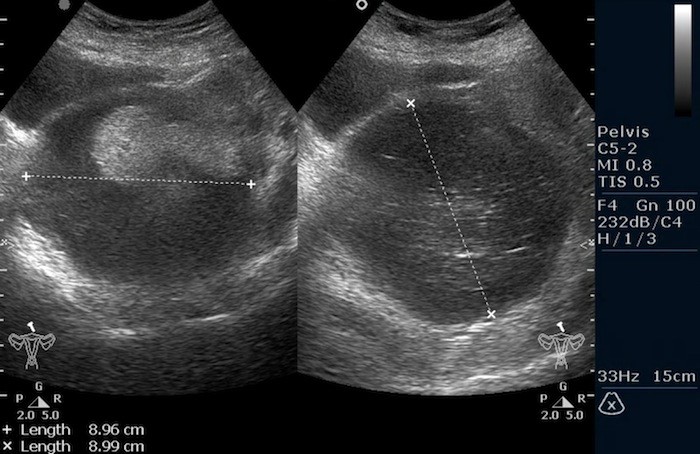

05.jpgТератома яичника (УЗИ малого таза)